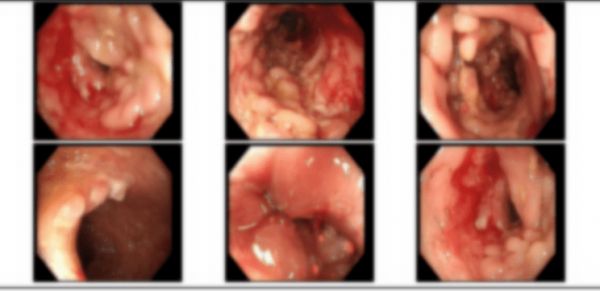

為明確診斷,小戴接受了腸鏡等檢查。

通過腸鏡檢查,金醫(yī)師發(fā)現(xiàn)小戴的多處腸道上分布著多個大小不等的潰瘍,腸道粘膜充血水腫,呈鵝卵石樣改變。后經(jīng)過病理檢查后,確診小戴為克羅恩病。